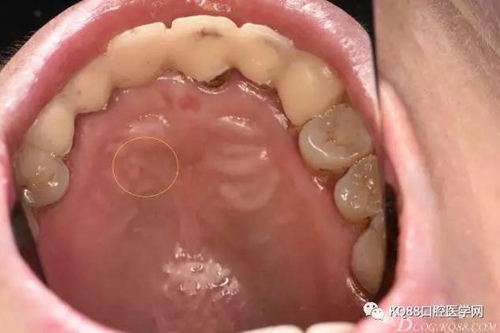

圖4.腭側(cè)觀:12根尖正對的腭粘膜隆起、有波動感